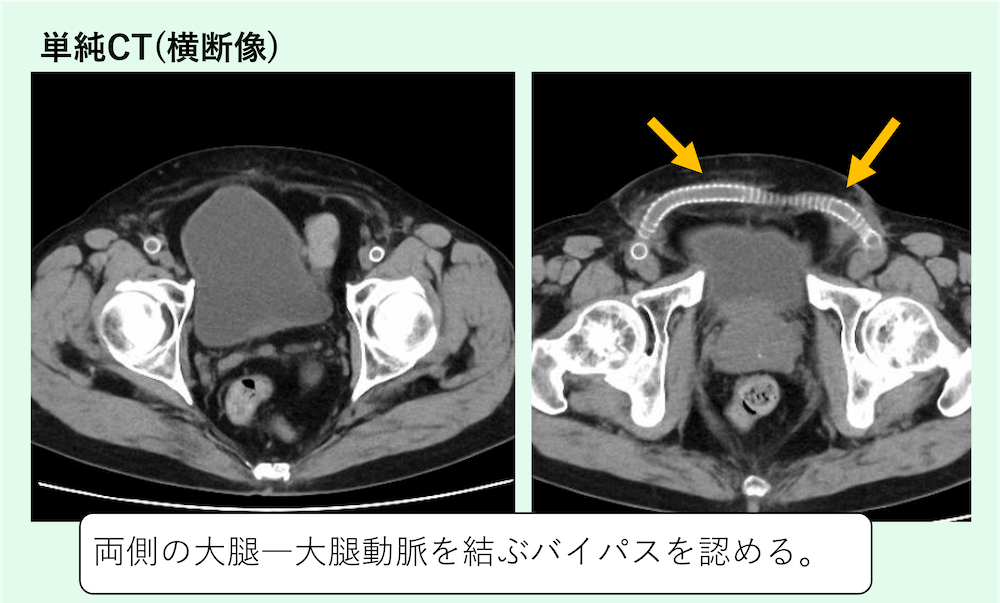

両側の大腿―大腿動脈を結ぶバイパスを認めています。

大腿―大腿バイパス術の正常なCT画像所見

合併症のないF-FバイパスのCT所見として、以下の点を確認する。

• グラフトの走行:人工血管は通常、腹直筋鞘の前方、皮下脂肪織内を恥骨結合をまたぐように「U字型」または「逆C字型」に走行する。皮下トンネル内にあるため、周囲脂肪織濃度の上昇が術後早期には見られるが、経時的に消失する。